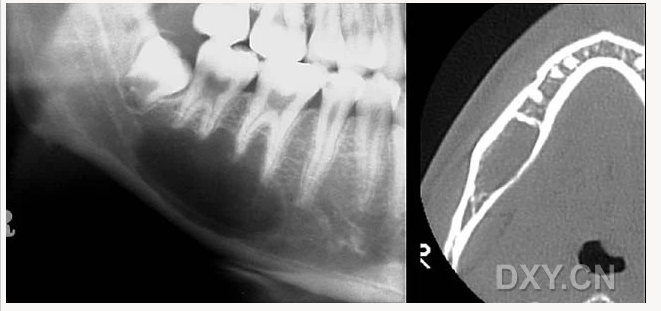

骨髓炎

頜骨骨折